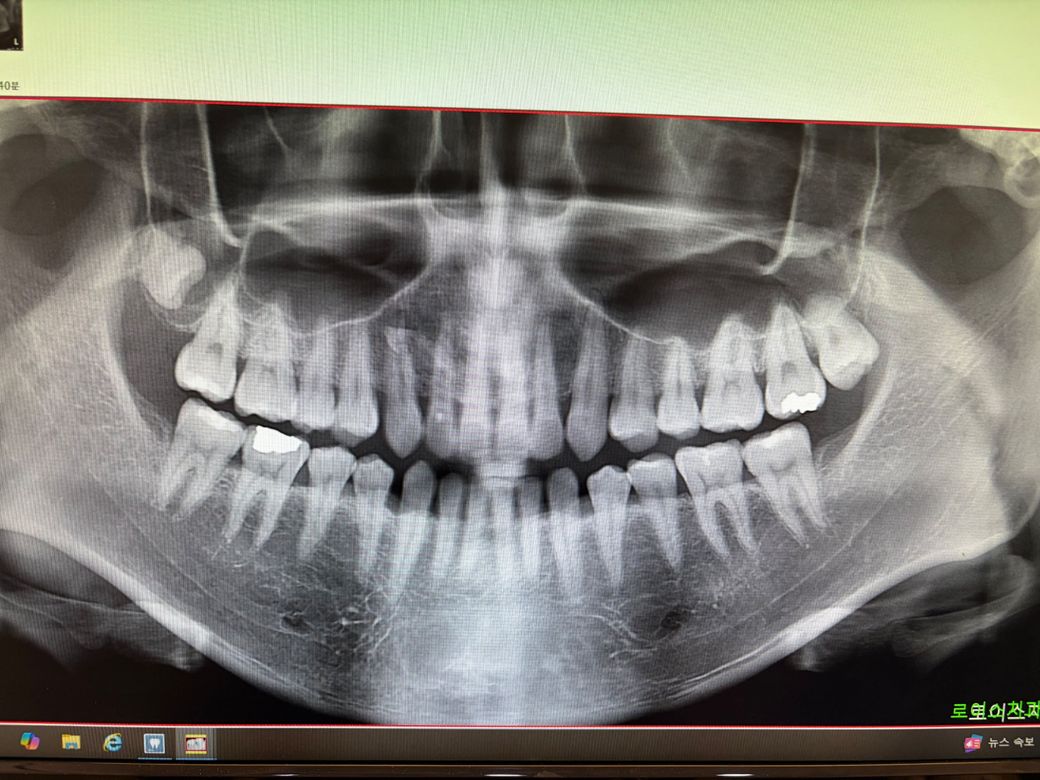

오른쪽은 안에있고 왼쪽은 어느정도 튀어나왔는지 잇몸? 끝쪽 살을 누르는 찌르는?느낌때문에 불편하네요 ㅠ 얼마전에 스케일링 받고 왼쪽은 뽑는게 좋을거같다해서 일단 반년뒤에 검사한번 받으로 가겠다고했는데 사랑니는 참 무섭네요 ㅠ

아 나이도 중요하다던데 삼십대 중반입니다.

왼쪽 위 사랑니는 보통 난이도인데 문제는 오른쪽이네요 위치가 아주 좋지 않아 일반 동네치과에서는 피할 것 같습니다